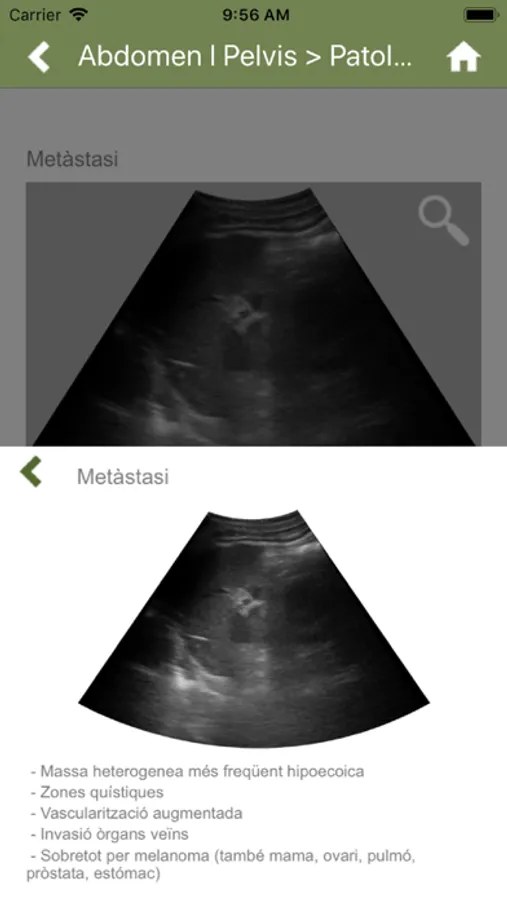

* Compilation of both anatomical and pathological images, with diagrams and illustrations.